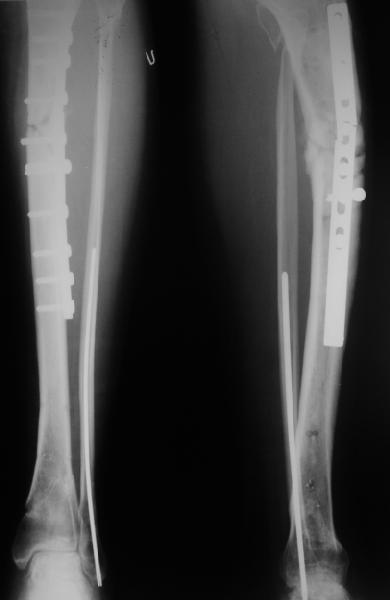

Декабрь 200322 июня 2004

В декабре прошлого года обсуждался случай бамперного перелома голени, когда молодой женщине в одной из больниц Москвы неудачно был выполнен остеосинтез гвоздем - это обсуждение можно просмотреть здесь, снимок тогдашний прилагаю.

Вчера поступила к нам в отделение. Клинически определяется приличная подвижность, градусов 35 в переднезаднем направлении. На снимках еще видны фиксированная тоникм стержнем уже сросшаяся малоберцовая кость, и тоже сросшийя перелом дистального метадиафиза большеберцовой костибез признаков хирургической фиксации (?). Сегодняшний снимок также в приложении.